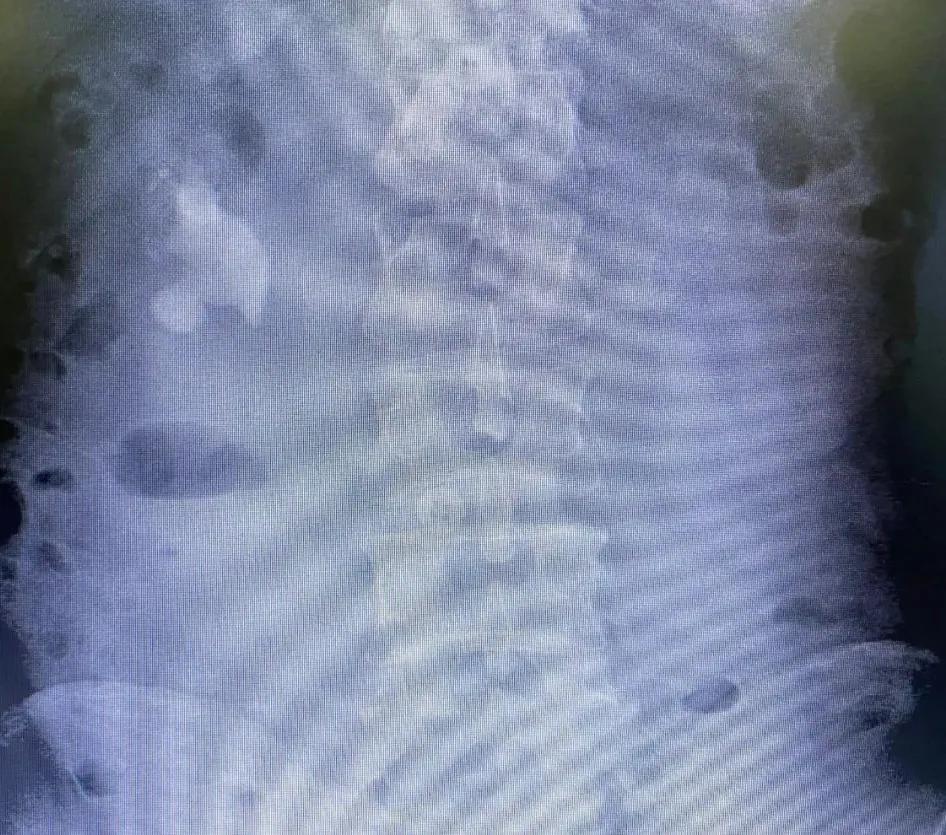

术前X光片

闫先生年龄不大,却已深受肾结石折磨长达三十余年,饱受痛苦。三十六年前,年仅十二岁的他因为右肾结石发作在当地医院做了开放手术切开取石,手术极其痛苦,恢复时间也很长,至今回忆起来还让他心有余悸。本以为痛苦已经结束了,没想到六年前体检时居然发现右肾结石再次复发,由于对手术的恐惧,他抱着一丝侥幸决定不再治疗。可惜,奇迹并未发生,六年来结石越长越大,到今年再次复查时已基本充满整个肾盂肾盏,再不治疗将严重损害肾脏功能。为了不再承受当年开放手术的痛苦,闫先生慕名到*警武**总院泌尿外科寻找庞栋主任,听说庞主任已经到门头沟区医院担任泌尿外科主任又辗转来到我院。

庞主任经过初步检查和评估,发现这个患者的情况非常复杂。巨大的肾结石不仅基本充满了整个右侧肾盂肾盏,而且患肾无明显积水,更糟糕的是三十六年前的开放性手术严重破坏了肾脏的解剖结构,导致此次手术的风险非常之大。但无论如何,既然患者慕名而来就绝不能辜负患者的信任,况且病情也不允许手术再拖延。